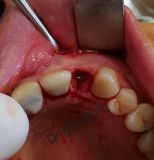

معرفی سیستم SPI همراه با جراحی زنده و Immediate Loading - آبان ۹۵

جراح وسخنران : استاد دکتر غلامعلی غلامی